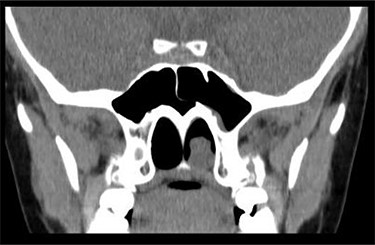

Anterior rhinoscopy revealed hypertrophied inferior turbinates with allergic nasal mucosa and increased nasal secretions with no mass seen. There was no active pus discharge from the nose. On throat examination, a large red, strawberry shaped mass was seen hanging posteriorly in the oropharynx. Flexible nasal endoscopy (FNE) of the left nostril was done, revealing a large polyp extending from the middle meatus into the choana and a clear right airway. A computerized tomography (CT) scan was done (Figs 1 and 2) showing a soft tissue mass arising from the left middle meatus, extending posteriorly and reaching the left choana (Fig. 2).

CT scan axial cut showing a large homogenous mass extending across the left nasal cavity.